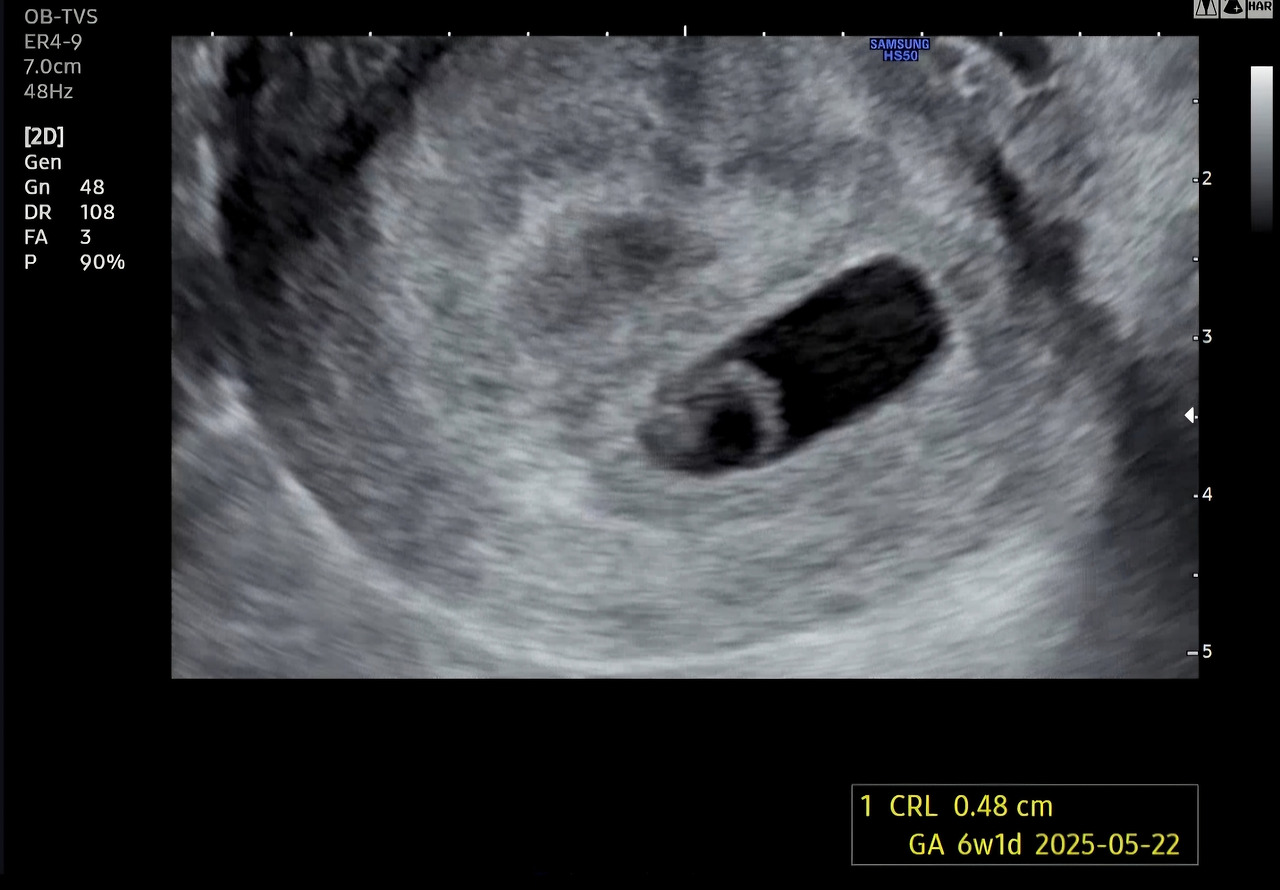

반지처럼 동그란 것이 난황이고 그 끝에 붙어있는 게 아기라고 하는데, 내 눈으로는 잘 식별할 수 없었다. 의사 선생님이 여기서부터 여기까지가 아기라고 화면에 표시해 주시며, 머리부터 엉덩이까지의 길이가 한 명은 0.6cm, 한 명은 0.48cm라고 했다.

6주 차에 확인한 초음파에서는 지난주보다 훨씬 공간을 늘린 두 개의 아기집과 동그란 난황 2개, 그리고 두 아이의 반짝이는 심장까지 볼 수 있었다.

아기의 모습은 잘 알아볼 수 없었지만 한 가지 확실하게 보이는 것은 심장의 깜박임이었다.